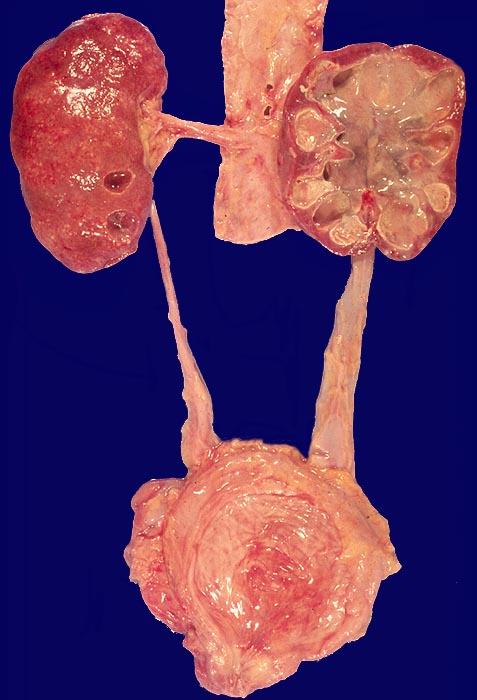

Pyonephrose und Pyoureter, akute Pyelonephritis

Im Vergleich zur kontralateralen Seite ist der Ureter ausgeweitet. Auch das Nierenbecken ist dilatiert. Die Niere wird durch grosse rundliche Nekroseherde weitgehend zerstört.

Steinbedingter Ureterverschluss

Sekundäre Pyonephrose als Folge einer infizierten Hydronephrose.